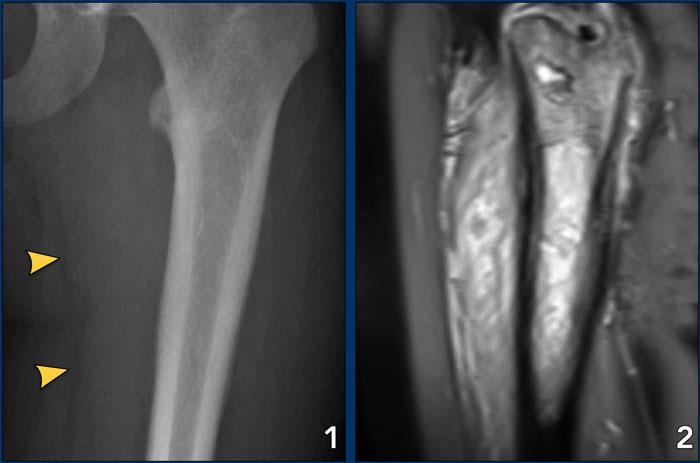

Bên trái là ba tổn thương xương với vùng chuyển tiếp hẹp.

Dựa trên hình thái học và độ tuổi của bệnh nhân, các tổn thương này là lành tính.

Lưu ý rằng ở cả ba bệnh nhân, các sụn tăng trưởng vẫn chưa đóng.

Images

- Non-ossifying fibroma

- Solitary bone cyst

- Aneurysmal bone cyst